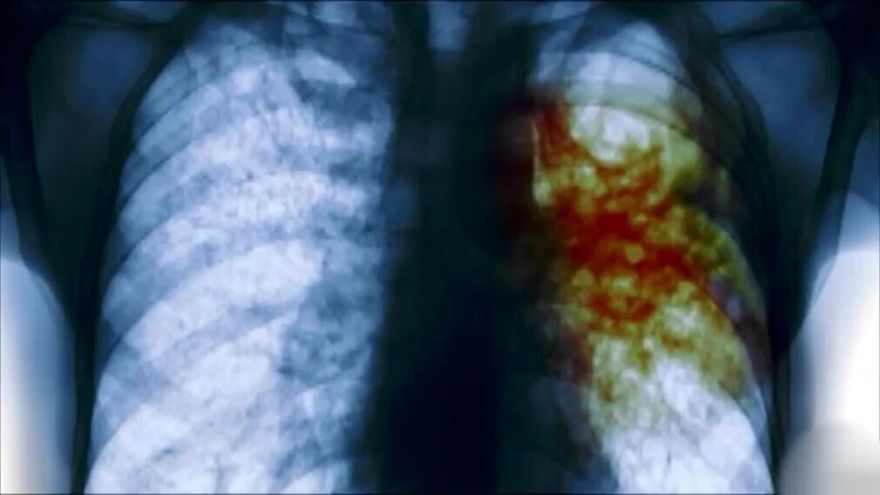

Captura de video: Una infección pulmonar

Captura de video: Una infección pulmonar / TVN Noticias

La tuberculosis es una infección bacteriana causada por un germen llamado Mycobacterium tuberculosis. La bacteria suele atacar los pulmones, pero puede también dañar otras partes del cuerpo.